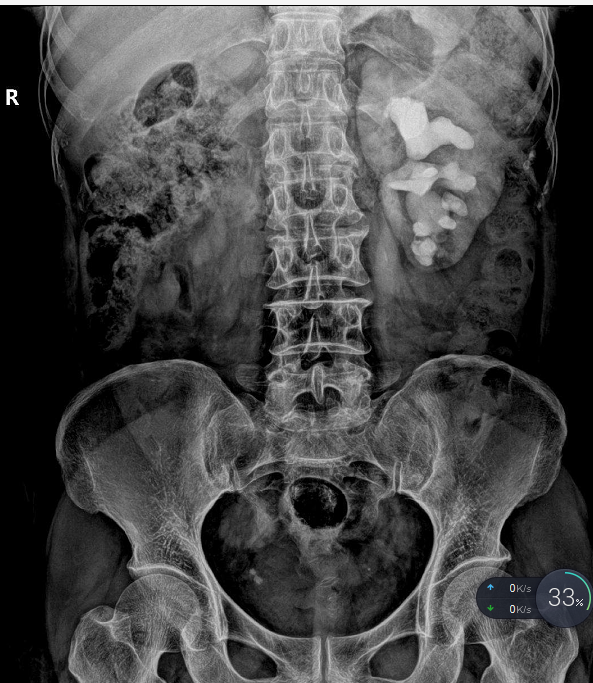

拍X线片、

血、尿常规等检查确诊。